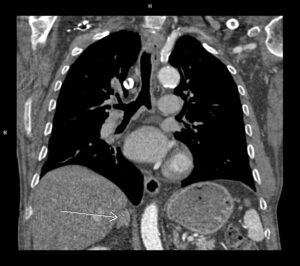

Discuţie caz nr 66:

Pacientul este scanat imediat posttraumatic în momentul zero și se pune în evidență creștere de volum a ligamentului încrucișat posterior în jumătatea distală cu întrerupere completă a continuității fibrilelor; deasemenea, se observă avulsie proximală a ligamentului colateral medial împreună cu un mic fragment osos din condilul femural intern.

Pacientul a fost scanat apoi la 2 luni posttraumatic și la un an posttraumatic și imaginile atașate sunt utile pentru a observa evoluția acestor leziuni.